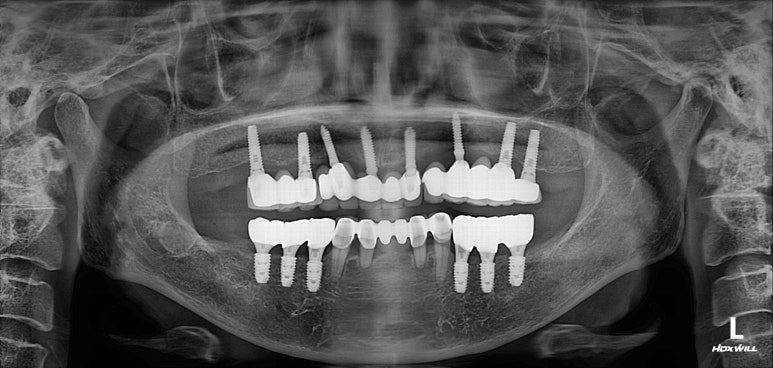

수술 후 촬영한 치과용 파노라마 사진에서, 정~말 깔끔하고 예쁘게 식립된 임플란트를 보실 수 있습니다.

아래턱뼈 내부에는 하치조신경이라는 감각신경이 주행하고 있는데요, 네비게이션 임플란트를 통해 수술 후 감각마비 없이 깔끔하게 마무리 되었습니다.

치과용 파노라마 사진을 보면 뭔가 좌우 대칭으로 깔끔하게 완성된 아래턱 양쪽 어금니 임플란트를 보실 수 있어요!!

치과용 파노라마 엑스레이만 보아도, 임플란트 여섯개가 깔끔하게 제작된 것을 보실 수 있을겁니다.